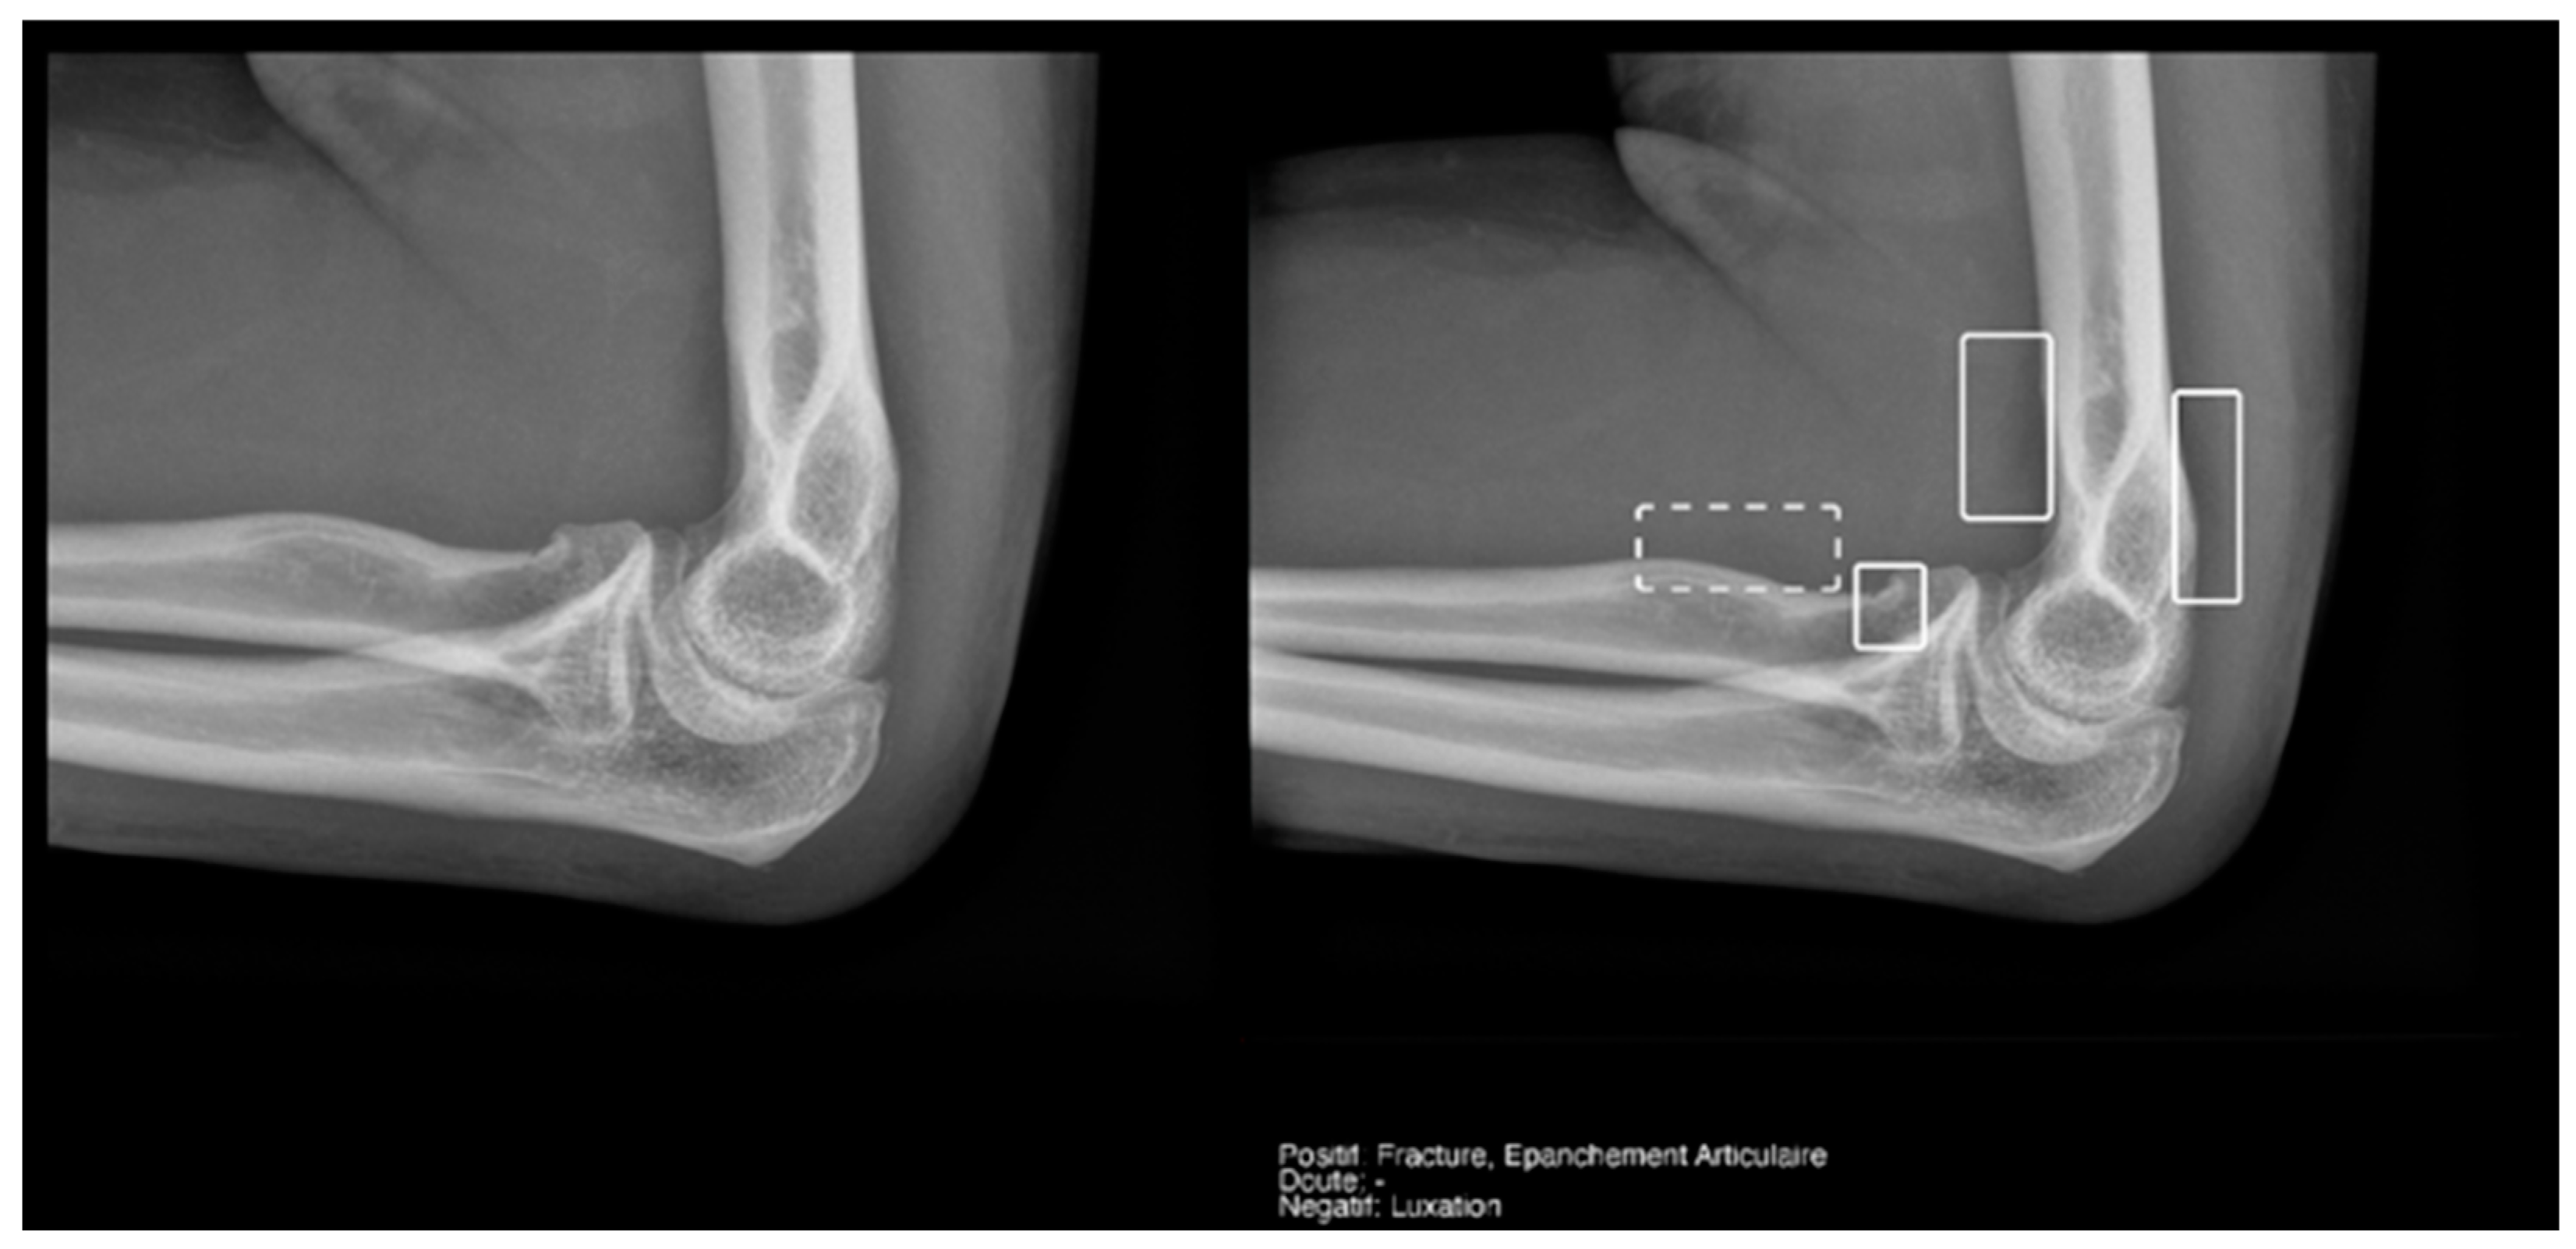

Regarding the detection of joint effusion in the elbow (Table 5), the low prevalence of joint effusion in our sample affected the calculation of the variables. Although a sensitivity of 100% was found in both the Milvue and the resident’s readings, the confidence intervals were very wide. On the other hand, specificity and negative predictive values were more reliable for both readings, with the AI reading standing out in particular, showing a specificity of 94.4% (Figure 12).

Figure 12.

Radial head fracture and joint effusion, correctly detected by AI and radiology resident.